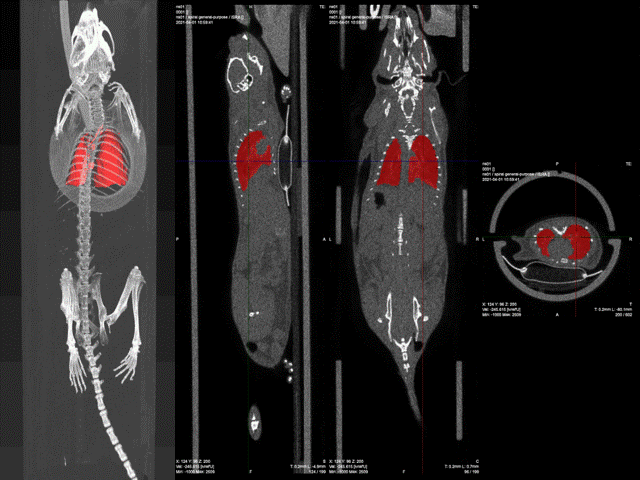

生活质量评分,小鼠行为学测试,小鼠呼吸功能测试(全体积描记),小鼠CT/PET-CT。

2.4 离体肺脏评价

Micro-CT,透明组织三维成像。